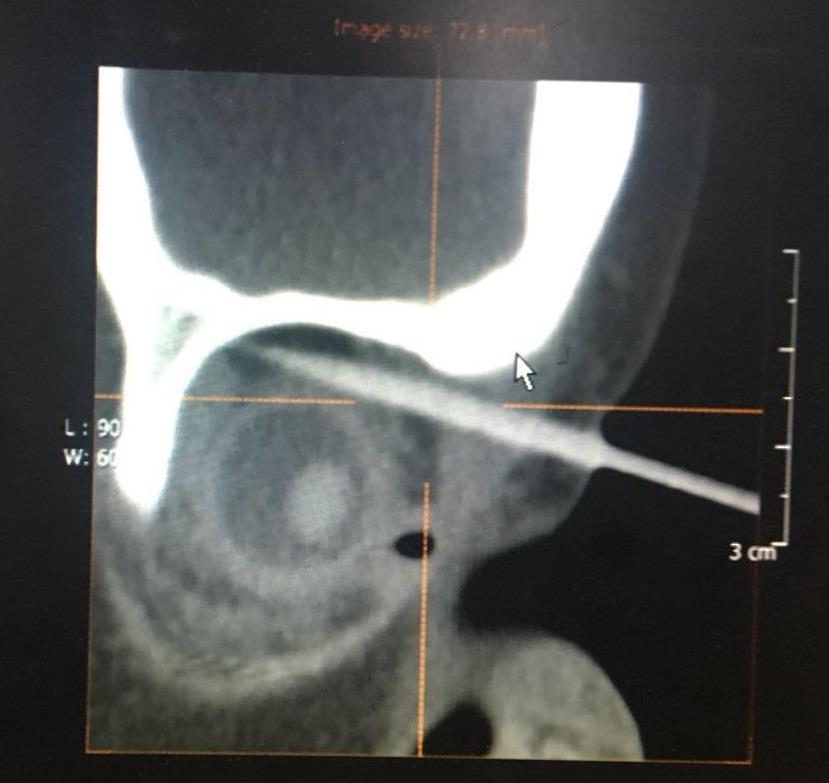

近日,我院眼科收住了一例特殊的小病人。当天下午近五点,一对焦虑而疲惫的夫妻急急地抱着一个明显哭过的小孩来到眼科,小孩2岁,鼻根部近右眼眶一根长长的竹签格外显目,外露的竹签不短,可是接诊医生查屹担心的是戳入的竹签:

幸运的是,经眼眶CT检查后确认竹签从鼻根部进入上眶缘,并未进入颅内,经过上直肌与眼球擦肩而过。然而,怎么取?这是一个问题,外侧竹签长,内侧短,根据杠杆原理,你在外面稍有移动,可能就在里面如秋风扫落叶一般,伤害到重要的血管、神经,甚至,导致失明。正所谓差之毫厘,失之千里,查医师首先建议全麻。然而,2小时前患儿已进食,全麻需禁饮禁食6小时以上。但这个2岁的小朋友在竹签的折磨,越发烦躁,哭闹不安,家属深怕竹签位置在小孩的挣扎下不断地往深处去,造成更大的损伤,强烈要求医生尽早取出竹签。